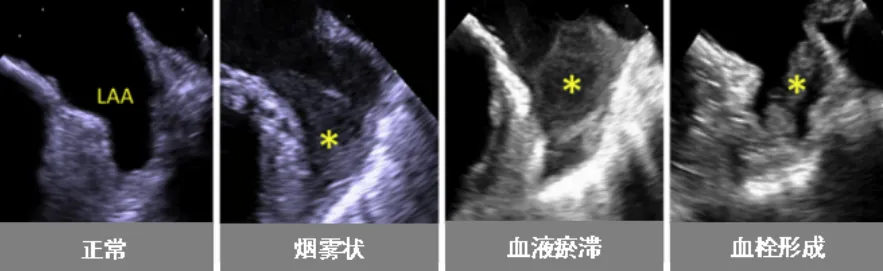

近日,皇冠足球投注网 (简称皇冠足球网 )超声医学科联合心血管内科为一名心脏病患者开展了经食管超声(TEE)检查。该项技术的开展,填补了皇冠足球投注网 在经食管超声领域的空白。患者黄阿姨(化名)今年59岁,几年前被诊断为“风湿性心脏病-二尖瓣中度狭窄”。近日,黄阿姨在医院复查心脏超声,报告提示风湿性心脏病-二尖瓣中度狭窄并中度关闭不全,且有左心耳附壁血栓形成可能(约3cm,游离端活...